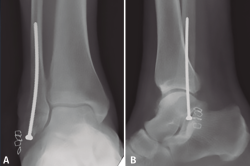

La osteosíntesis endomedular del peroné está descrita con diferentes tipos de tornillos, siendo los más utilizados en la literatura los tornillos de 3,5, 4,2 o 4,5 mm(17). Nuestra preferencia personal es la utilización de un tornillo cortical de 3,5 mm largo, de 80 a 120 mm de longitud (de la caja de pelvis), debido a la mayor flexibilidad del implante y la capacidad de adaptación al canal medular(52,55)(Figura 4). Este tornillo puede permitir incluso la reducción del desplazamiento lateral del fragmento distal del peroné con el punto de entrada adecuado en la punta del peroné(55). Esta técnica también permite espacio para añadir un tornillo para la estabilización de la sindesmosis(17,53).

Figura 4. Tornillo intramedular de peroné (cortical de 3,5 mm). Nótese la flexibilidad del tornillo y la capacidad de adaptación a la cavidad medular.

Respecto a esta técnica, debemos diferenciar 2 conceptos: por un lado, el uso de tornillo intramedular percutáneo aislado, con el beneficio de menores complicaciones de partes blandas. Pero, por otro lado, esta técnica puede usarse combinada con la osteosíntesis convencional como método para aumentar la estabilidad de la construcción (Figura 5), tanto con el uso de tornillo intramedular (a través o fuera de placa) como con el uso de agujas de Kirschner endomedulares. Koval(56) realiza un estudio clínico y biomecánico demostrando el beneficio de añadir 2 agujas de Kirschner endomedulares a la osteosíntesis convencional para el tratamiento de fracturas osteoporóticas y conminutas. En el estudio biomecánico, la resistencia al doblado aumentaba en un 81% y la resistencia a la torsión era del doble, al añadir las 2 agujas de Kirschner de 1,6 mm en comparación con la placa aislada. En el estudio clínico, presenta una serie de 19 pacientes mayores de 50 años con osteopenia y/o conminución tratados con esta técnica, con correcta consolidación en todos los pacientes. Entre las complicaciones, 2 pacientes precisaron retirada de material (uno por migración de las agujas) y un paciente diabético presentó retraso en la cicatrización de la herida(56).

Figura 5. Placa de tercio de caña con refuerzo de tornillo intramedular (canulado de 4,0 mm).